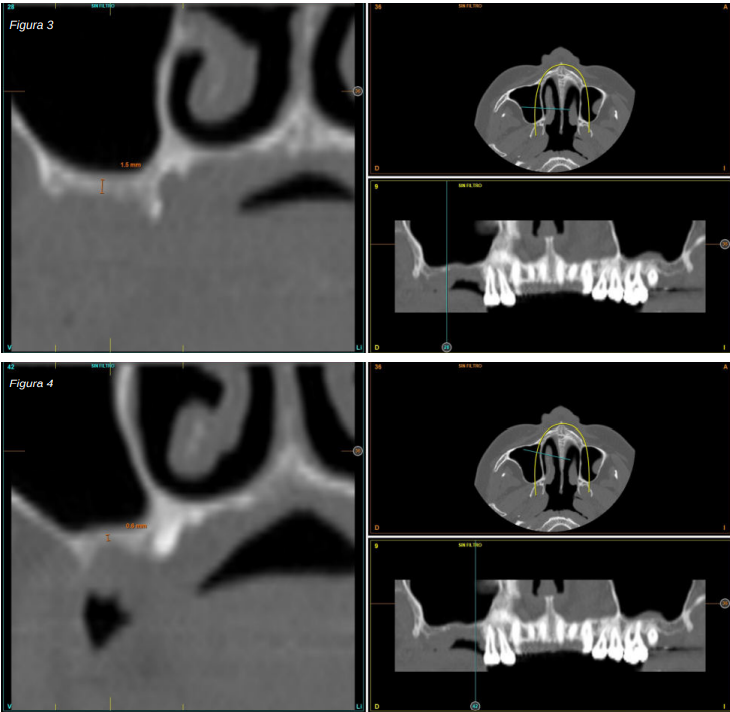

Transcurridos cuatro años, los molares del segundo y tercer cuadrante comienzan a tener una movilidad excesiva y problemas periodontales graves, por lo que se decide la extracción de los mismos y la regeneración de los alveolos con PRGF-Endoret. Una vez regenerada la zona (mes y medio después) se procede a la obtención de un Cone-beam para evaluar el volumen óseo residual. En el mismo se puede observar cómo existe una cresta ósea desigual con zonas de 3,3 mm de altura hasta 7 mm como máximo (Figuras 9 y 10). En esta ocasión, debido al cambio de protocolo descrito anteriormente, se opta por la inserción de implantes extra-cortos de forma directa, ya que los protocolos quirúrgicos para abordar este tipo de situaciones en el año 2011 variaron sustancialmente, siendo estos implantes una herramienta de primera línea para el tratamiento de este tipo de atrofias (Figura 11). Se seleccionan dos implantes extra-cortos (5,5 mm de diámetro x 6,5 mm de longitud para la pieza dental número 26 y 6 mm de diámetro por 5,5 mm de longitud para la pieza dental número 27).